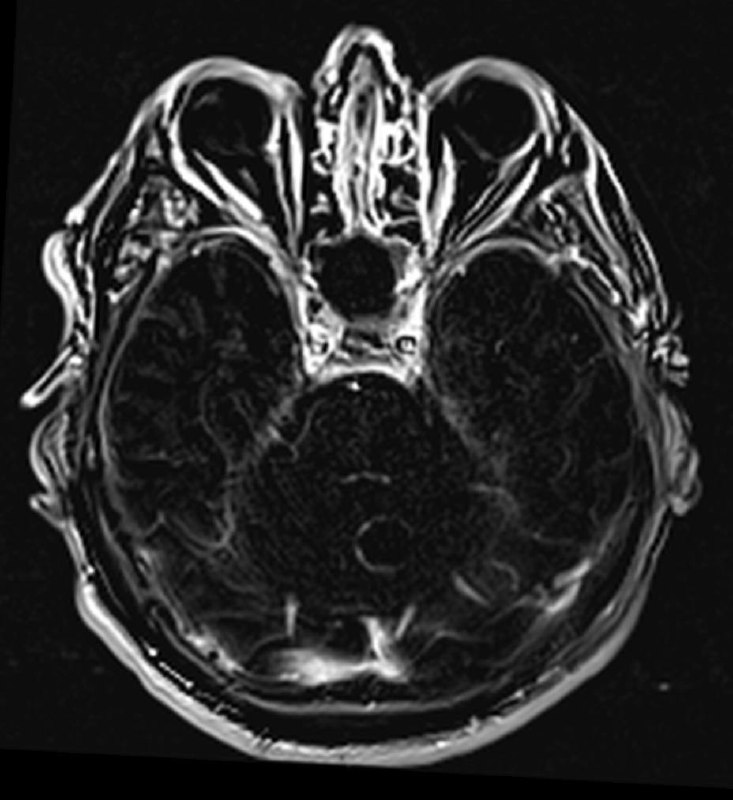

Пациент 35 лет. Жалобы на онемение правой руки. Других жалоб нет.